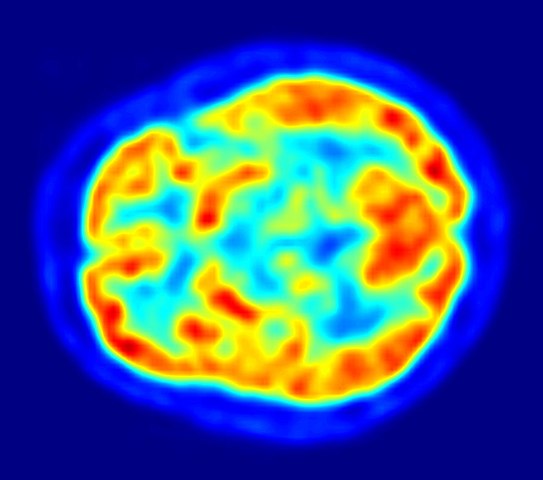

Diagnosing Autoimmune Encephalitis

For a difficult-to-diagnose disease, PET imaging may offer better insight than MRI